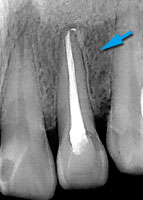

虫歯が神経まで進行してました。

神経を抜いた後、根尖まで緊密に充填します。